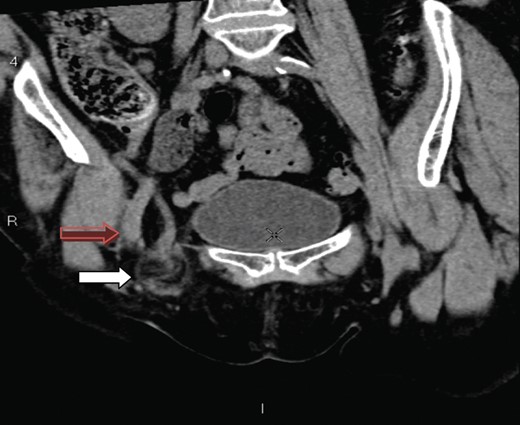

A coronal section showing the tip of the appendix (white arrow) protruding through the femoral canal, medial to femoral vein (red arrow) into the hernia. The appendix measures 10 cm.

The presence of an appendix within the femoral canal can be explained by the presence of an abnormally low/large caecum which causes the appendix to have a pelvic location [4]. The CT findings in our patient show a very long appendix (10 cm) extending from an anatomically normal caecum with the tip extending through the femoral canal and explains another plausible mechanism for a de Garengeot's hernia. The aetiology of appendicitis has long been recognized as due to intraluminal obstruction either by a fecolith, worms, tumours or lymphoid hyrperplasia [7]. It is also possible that the rigid and narrow confines of the femoral canal can lead to extraluminal obstruction of the vermiform appendix and lead to ischaemia, inflammation, necrosis and subsequent perforation.